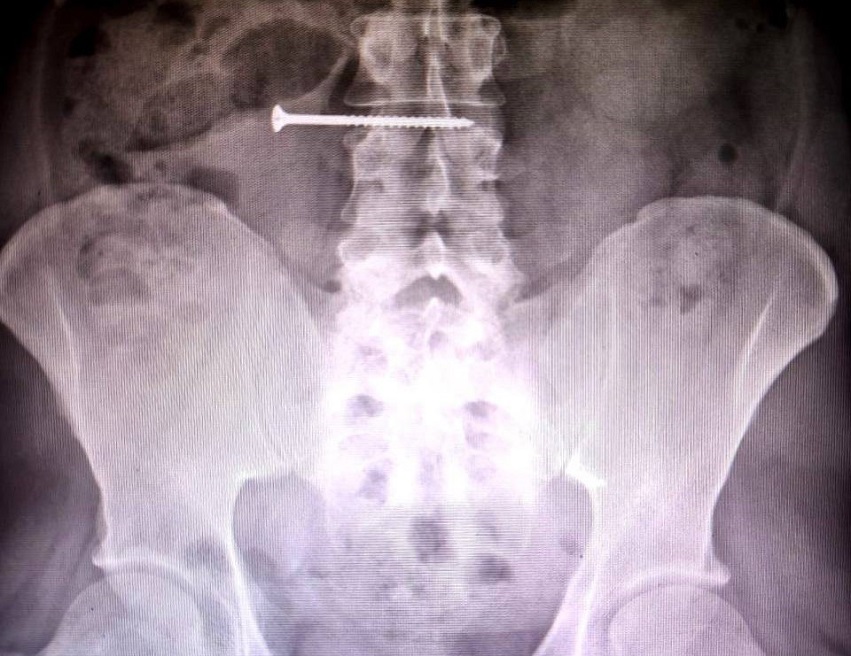

В Красноярскую краевую больницу обратился красноярец, который случайно проглотил пятисантиметровый саморез. Об этом пишет gnkk.ru со ссылкой на пресс-службу клиники.

Мужчина обшивал дом сайдингом и держал во рту саморезы. В какой-то момент он оступился и проглотил один из них.

Снимки показали, что инородное тело длиной 50 миллиметров дошло до тонкого кишечника. Опасность ситуации была в том, что саморез мог сделать сквозное отверстие в стенках органов.

Красноярца экстренно прооперировали. Контрольное обследование показало, что повреждений стенок желудка и кишечника нет. На данный момент мужчина находится в отделении хирургии под наблюдением врачей.